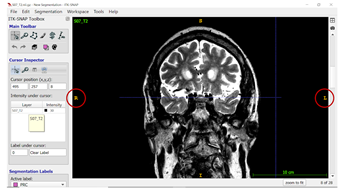

- Slice Numbers: When you scroll through the slices, the slice number at the bottom right corner increases as you from anterior to posterior in the brain (and you will segment from anterior to posterior).